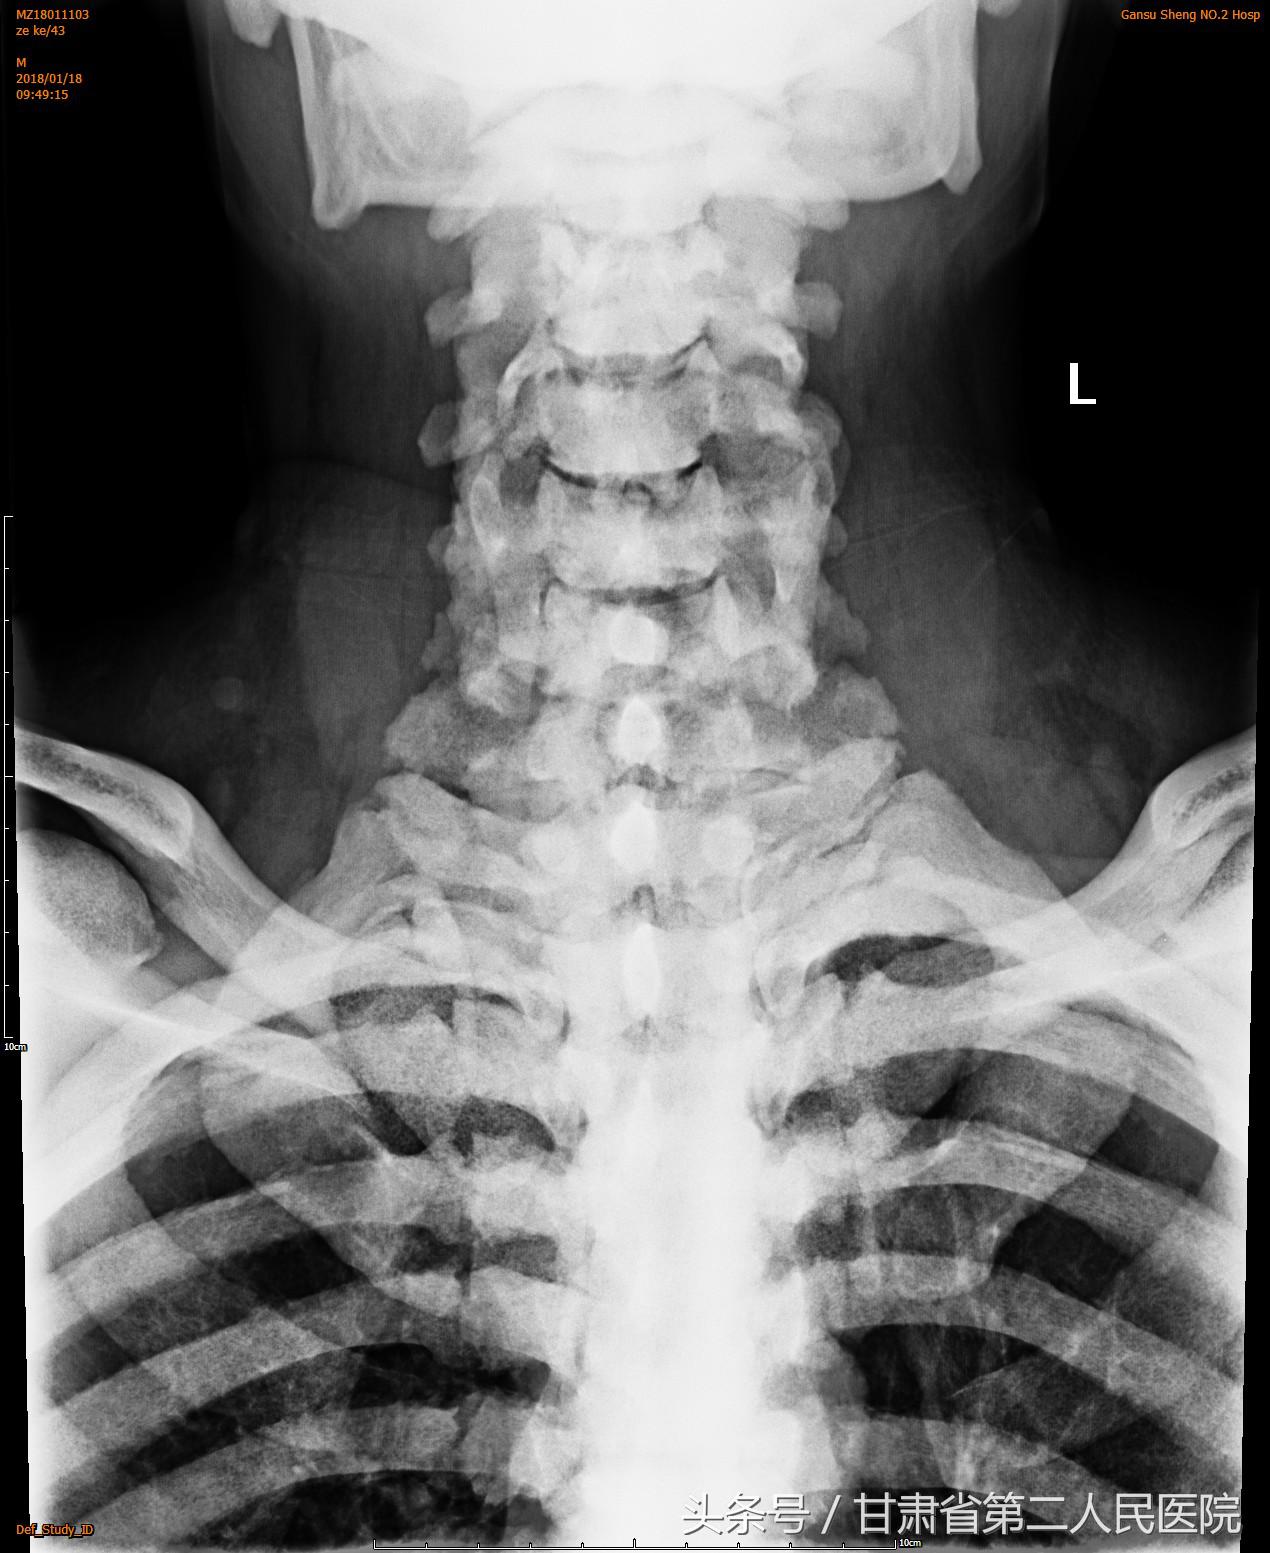

入院后行全脊柱X线、CT及MRI示:C3-6颈椎后纵韧带骨化引起的脊髓型颈椎病,并有严重的石骨症。

可见全身骨质密度均匀增高,符合石骨症表现